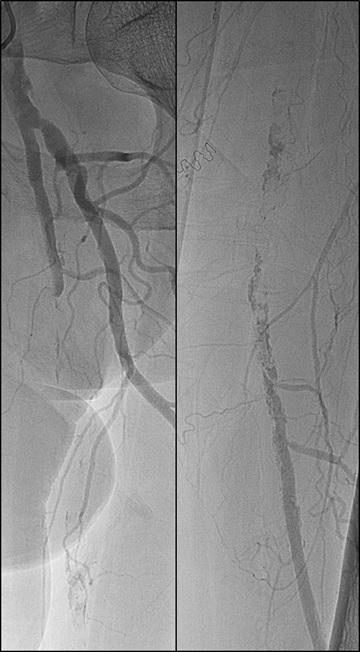

1. CTO of the left superficial femoral artery in a male patient suffering from severe claudication in the left calf

2. After subintimal passage, it was impossible to redirect the guidewire into the patent lumen distal to the CTO

3. Positioning of the BeBack catheter to re-enter the guidewire. Arrow indicates an orientation-marker

4. Marker appearing as a “C” indicates the direction of the needle, with the needle protruding maximally out of the BeBack catheter

5. An 0.018” guidewire passing into the patent distal lumen

6. Result after stenting